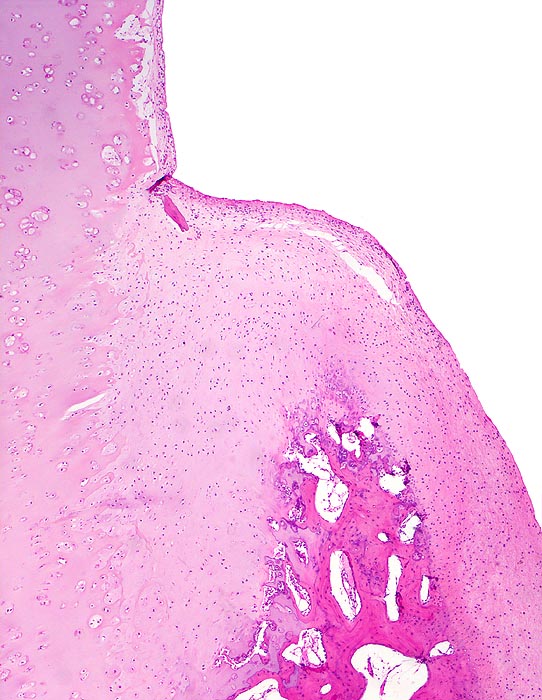

• Sekundäre Sklerose der freiliegenden Spongiosa mit Anbau von breiten Faser- und Lamellenknochensäumen an die alten Bälkchen.

• Leichte Osteoporose in der craniolateralen Entlastungszone.

• Herde von metaplastischem Faserknorpel in der Gelenkfläche.

• Randosteophyt, welcher über Resten des dort noch vorhandenen Gelenkknorpels entstanden ist (Verdoppelung des Knorpels).

• Nekrosebezirk in der Spongiosa (Geröllzyste) umgeben von einem Granulationsgewebssaum und Narbengewebe.